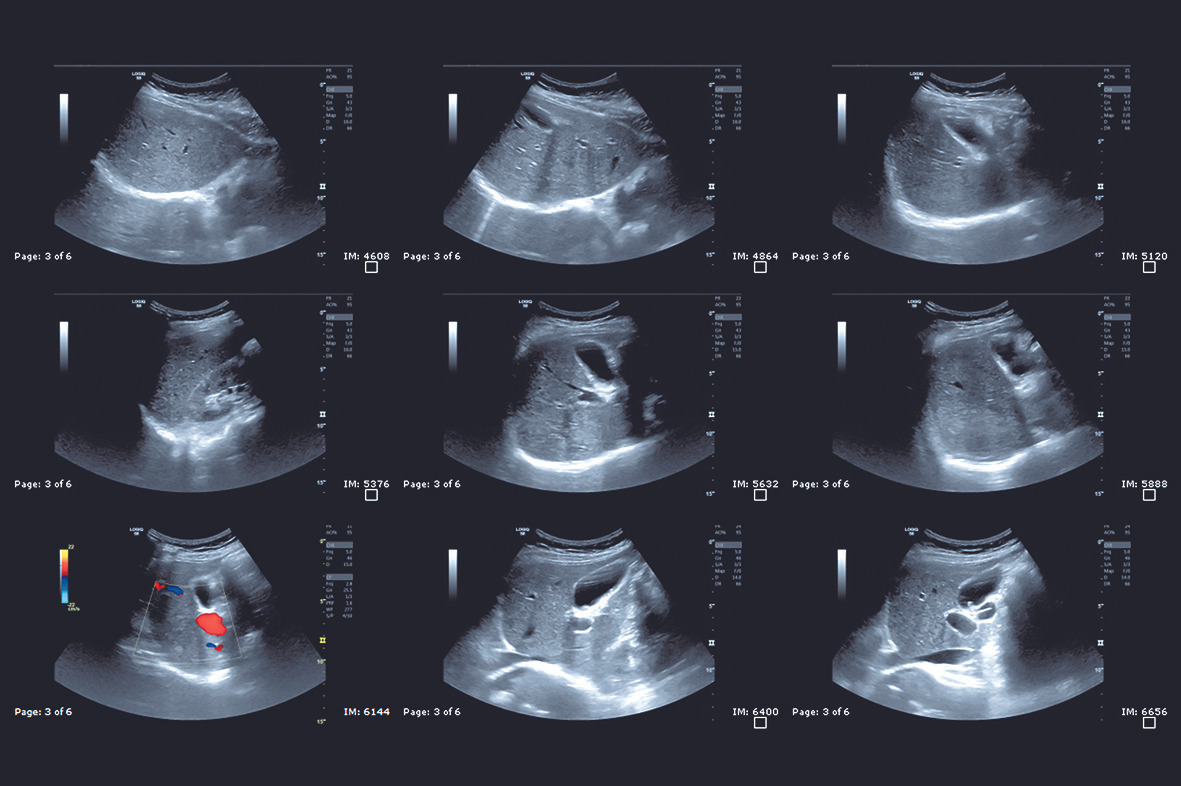

복부 초음파(Abdominal Ultrasound)는 인체에 해가 없는 음파, 즉 초음파를 사용하여 간, 담낭, 신장, 비장, 췌장 등 복부 장기의 형태와 상태를 확인하는 검사입니다. 흔히 “초음파와 방사선 관계”를 궁금해하시는 분들이 있는데, 기본적으로 초음파는 방사선(X선)을 사용하지 않습니다. 따라서 임신부도 안심하고 검사를 받을 수 있으며, 여러 번 반복해도 방사선 피폭에 대한 걱정이 없다는 것이 큰 장점입니다.

결과 영상을 보면 까만색, 회색, 흰색 영역이 모자이크처럼 보이는데, 이를 통해 장기의 경계, 혹이나 낭종 여부 등을 판별할 수 있습니다. 예를 들어 “신장에 혹과 낭종의 차이”를 진단할 수 있는 것도 초음파로 비교적 쉽게 확인이 가능합니다. 최근에는 해상도가 높은 장비들이 많이 보급되어, 수 밀리미터 단위의 이상도 찾아낼 수 있어 더욱 믿음이 가는 검사죠.

복부 초음파는 상당히 다목적 검사로, 여러 장기의 상태를 종합적으로 확인할 수 있습니다. 복부 초음파로 알 수 있는 것은 어떤 것들이 있으며 복부 초음파로 알 수 있는 질환들이나 이상 신호들을 체크할 수 있는지 구체적으로 살펴볼까요?